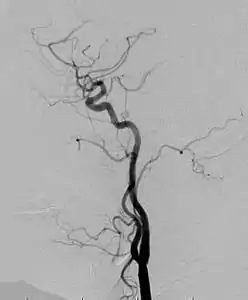

Angiogram: an angiogram can also be ordered to get a detailed look at the blood vessels in the affected or overgrown limb. In this test a physician injects a dye into the blood vessels that will help see how the blood vessels are malformed.[23]

MRI-dilated turtuous blood vessels

Angiogram